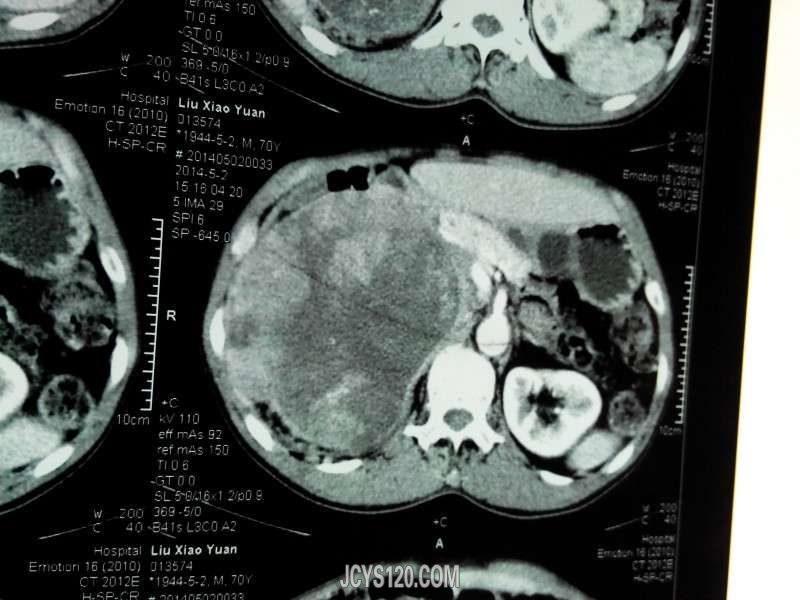

患者女性,70岁,体检发现,大家诊断什么病,怎么治疗。谢谢!